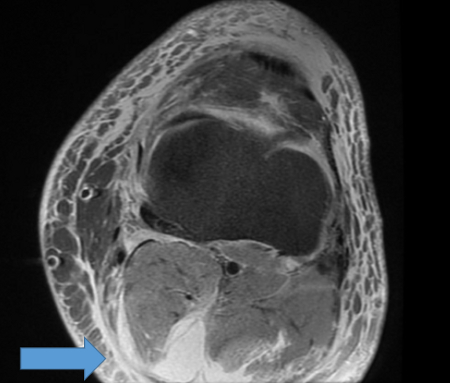

A ruptured haemorrhagic popliteal cyst extending in the calf

Stony Brook University Medical Center private collection; used with permission